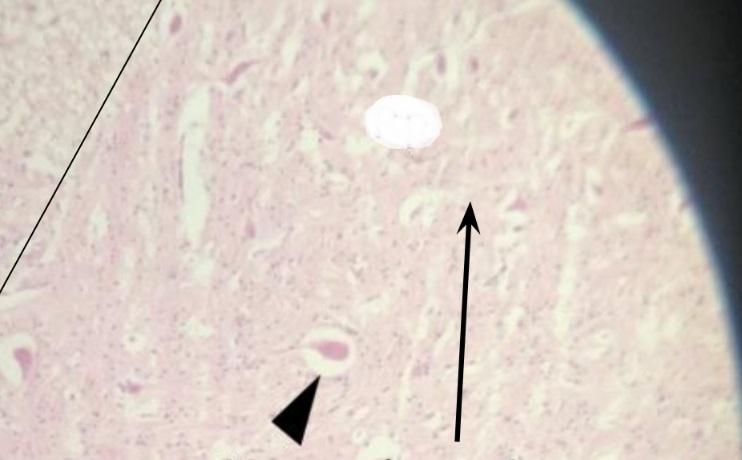

Pytanie 150

istota biała (rdzeń kręgowy)

Pytanie 151

kanał centralny (rdzeń kręgowy)

Pytanie 152

nabłonek ependymalny - jednowarstwowy walcowaty (rdzeń kręgowy)

Pytanie 153

Pytanie 154

istota szara (rdzeń kręgowy)